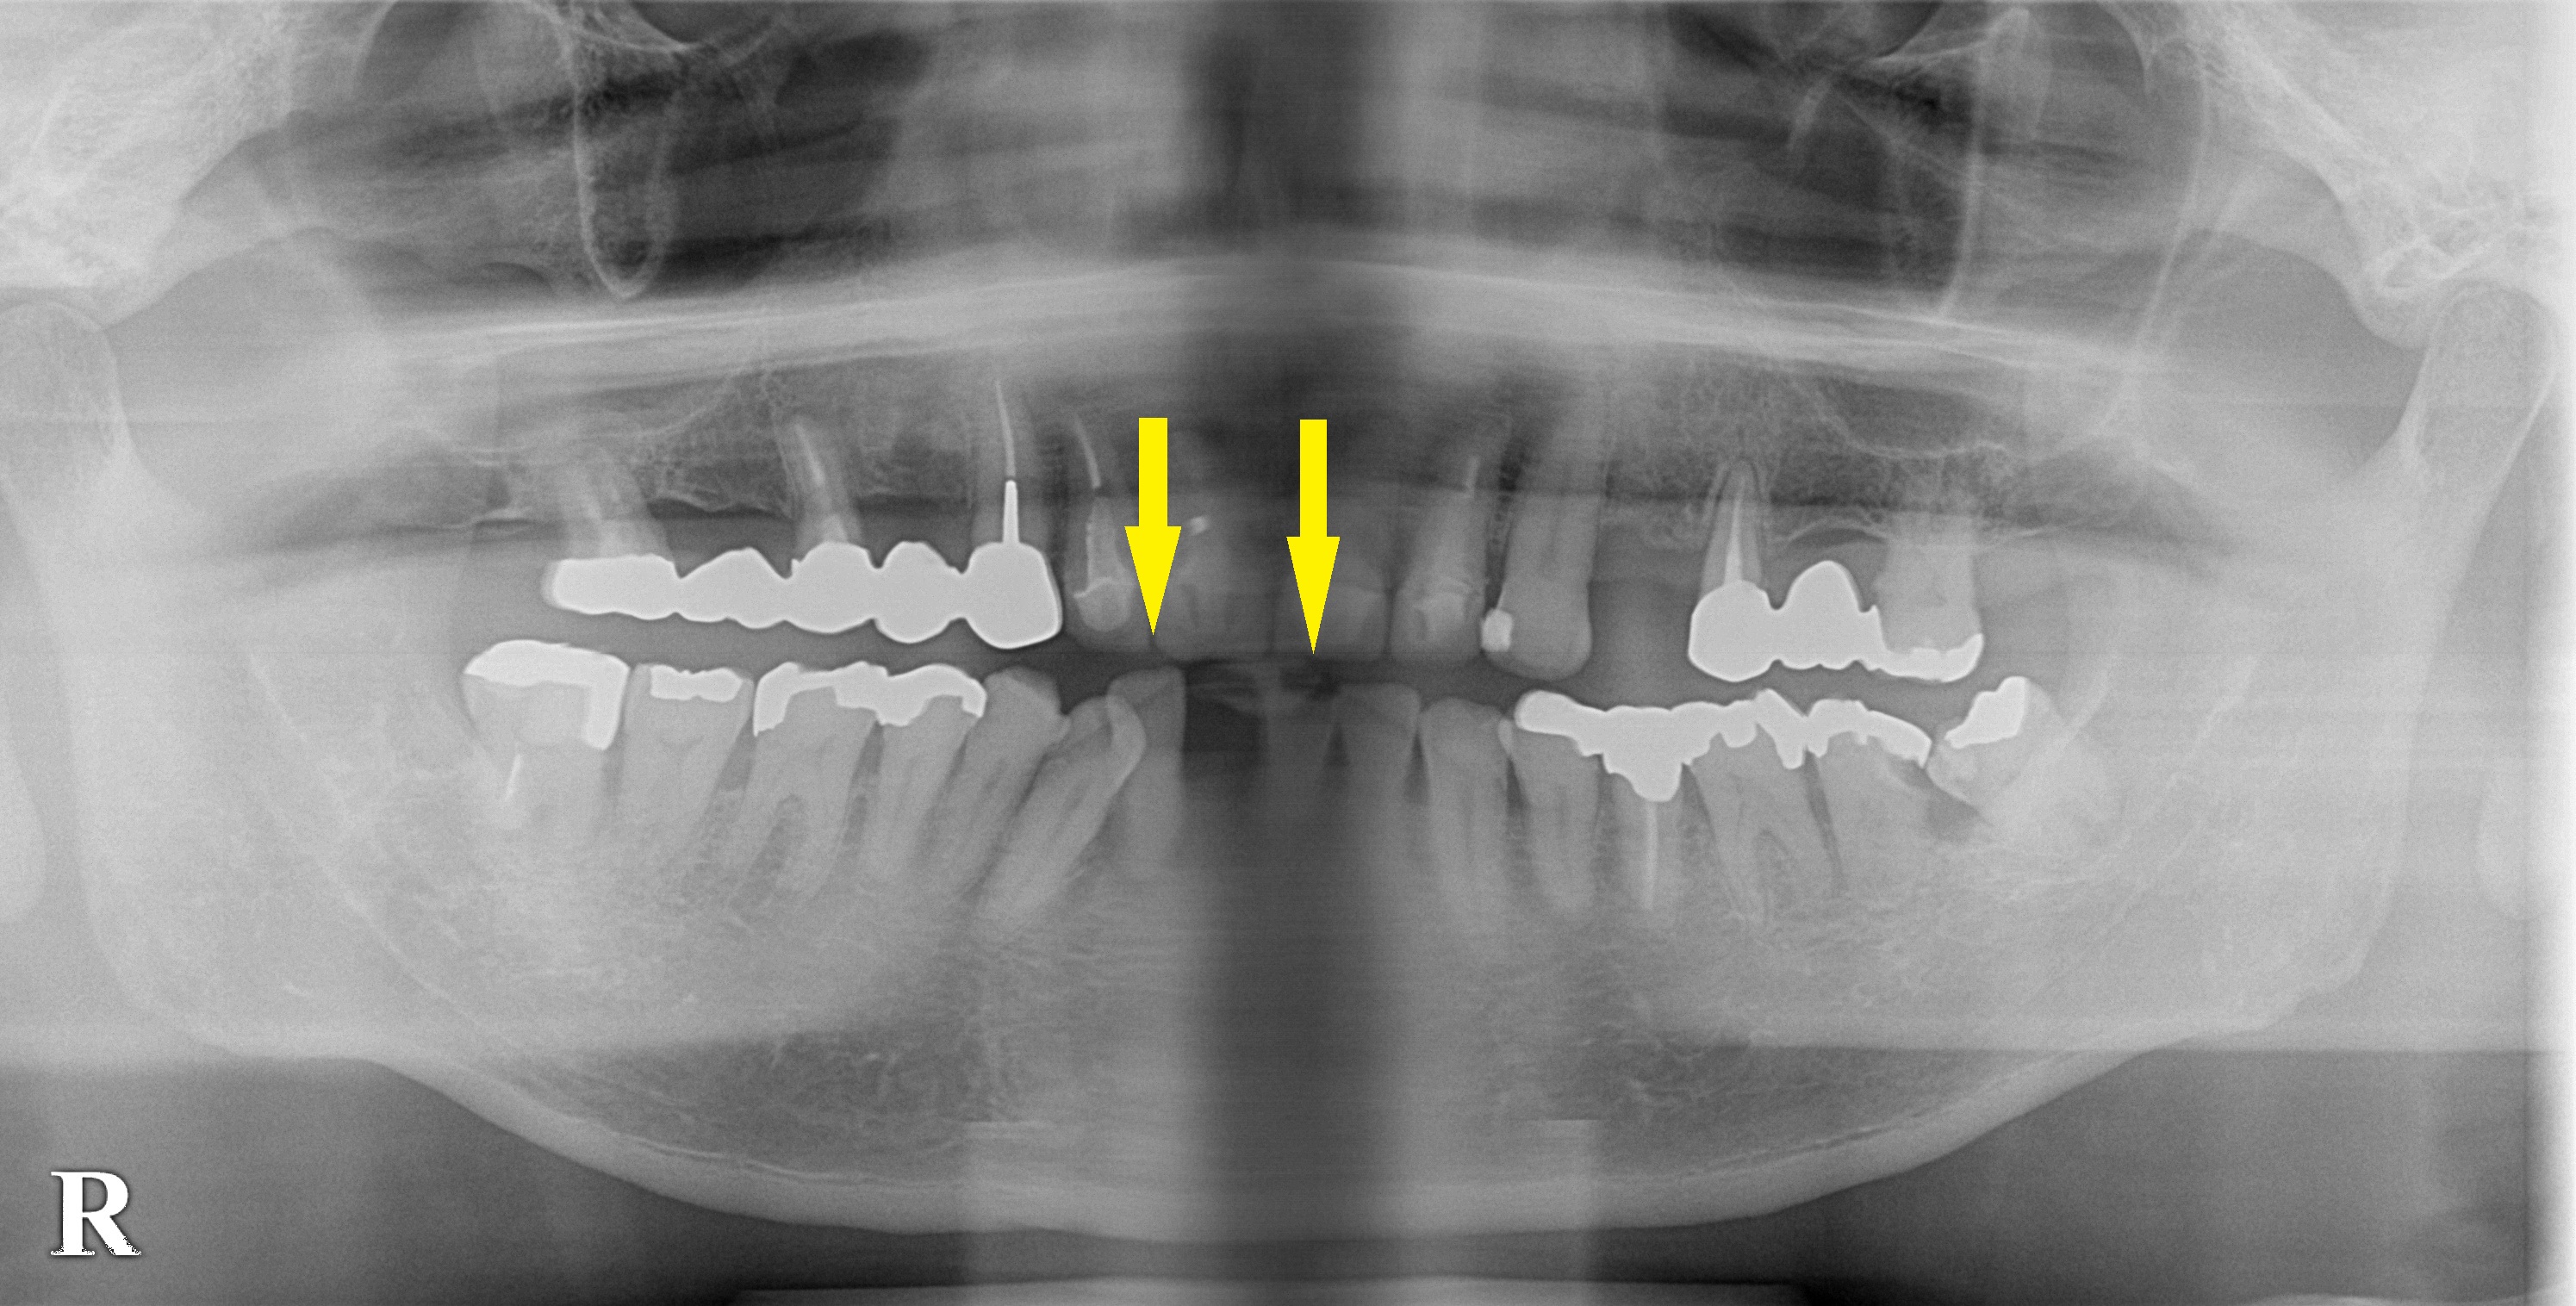

下顎前歯1本が以前から抜けたままになっていたのですが、その両隣の歯もグラグラしてきたために、もう何とかしなければならないと考えて相談においでになりました。

両隣の歯は、両方とも重度の歯周病で残すのは困難でした。

抜歯して、治癒を待ち、インプラント治療となりました。

下顎前歯3本の欠損に対し2本のインプラントを埋入しブリッジタイプで3歯を回復することとしました。

本日、インプラント埋入術を施行、下顎前歯部なので細めのサイズのインプラントを2本埋入しました。